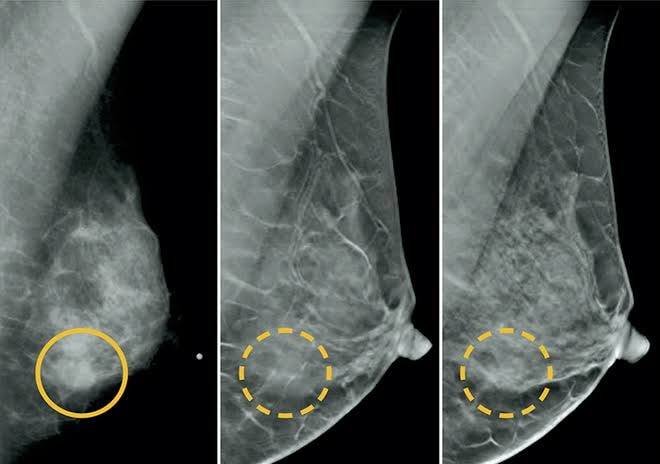

imagem sem descrição.

A Secretaria Municipal de Saúde de Itueta em um esforço conjunto com o poder executivo Municipal, disponibilizando aporte financeiro do recurso próprio, para liberar no mês de setembro de 2019 toda a sua demanda reprimida de exames de mamografia que se encontra em nosso TFD. Tendo em vista que o SUS realiza apenas 15 exames mês, e a nossa demanda ultrapassa 150. Seguimos firmes em nossa proposta de gestão junto ao prefeito municipal, Sr. Valter José Nicoli, que vem dando total apoio e esforçando a cada dia para levar a população de Itueta a melhor qualidade de serviços na saúde pública. Prevenir é a melhor saída. "O melhor é fazer! "